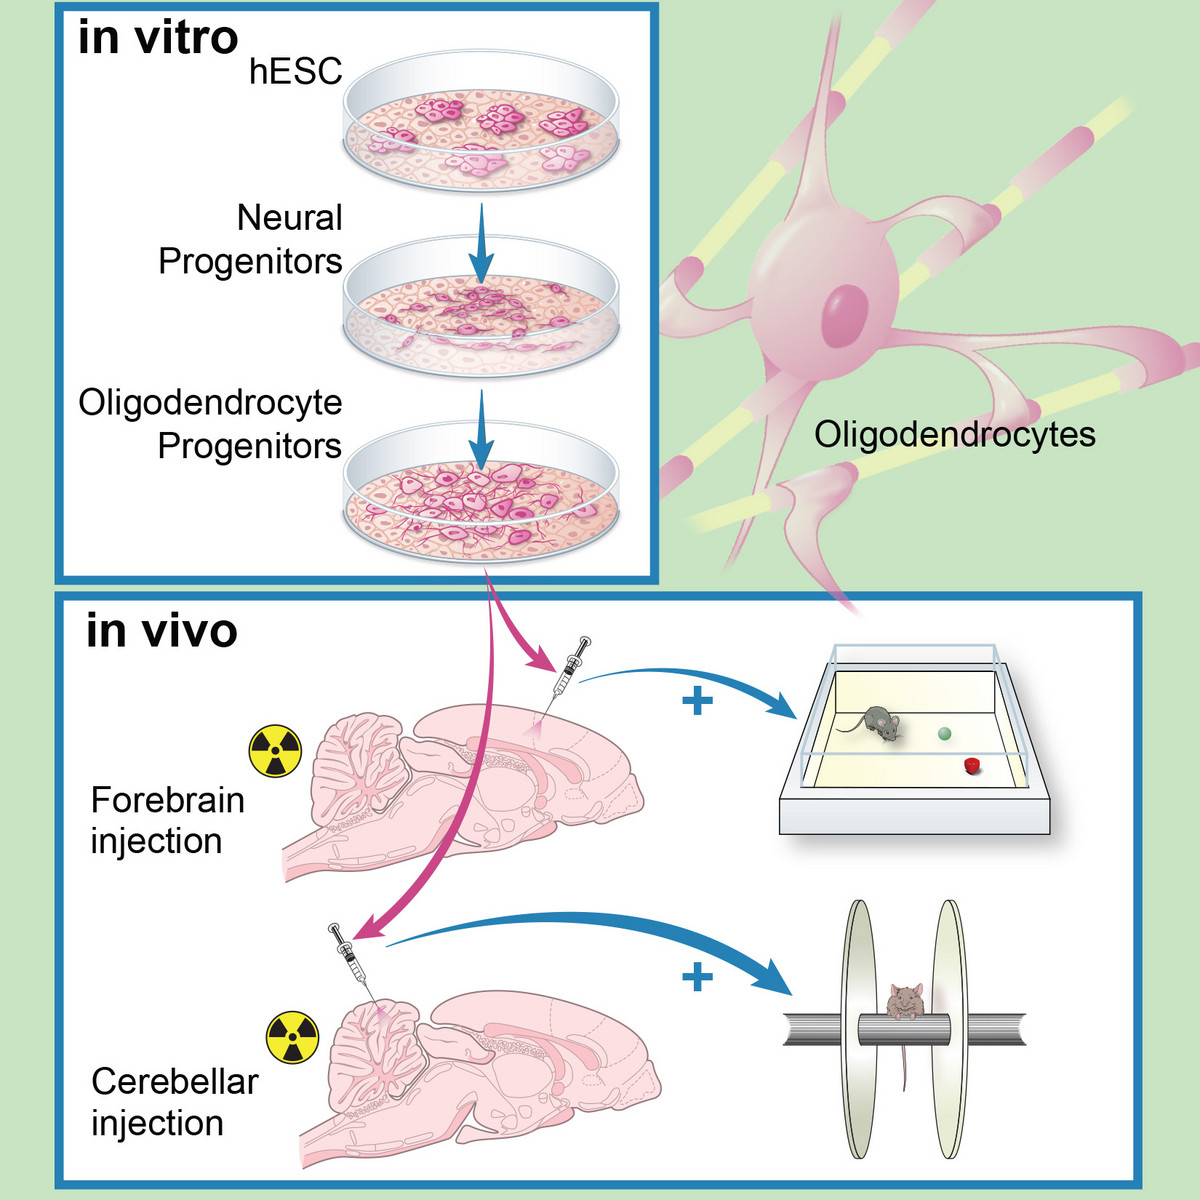

Human ES-derived grafts for repair of radiation injury

Radiation to the brain is a major contributor to poor quality of life among cancer survivors, yet it remains among the most potent tools in cancer therapy. Whole or partial brain radiation is a cornerstone of the treatment of many brain tumors, primary or metastatic, as well as a major component of prophylactic regimens in the treatment of leukemias. Young children are particularly vulnerable to the side-effects of radiation injury and often receive suboptimal radiation doses as a compromise between efficacy and safety. We have shown that radiation to the brain results in loss or significant depletion of the oligodendrocyte progenitor pool in the brain, both in a rat model we developed as well as in human brain tissue samples. We have also developed a scalable protocol for the efficient derivation of oligodendrocyte progenitors from human ES or iPS cells. The cells are well characterized by phenotype markers, gene expression profile and in vitro myelination. In a major effort over the past several years, we optimized rodent brain radiation to mimic the standard high dose fractionated regimen given to patients (50 Gy). The young rats develop cognitive and motor behavioral deficits within several months of treatment. Analysis of the rat brains shows depletion of the oligodendrocyte progenitor pool as well diffuse demyelination. Grafting resulted in structural repair shown histologically and by electron microscopy, as well as in a graft region-specific behavioral improvement. Forebrain grafts improved cognition while cerebellar grafts were required for amelioration of motor balance3. We plan to further optimize the cell culture and in vivo parameters in future pre-clinical studies.

Human ES derived oligodendrocyte progenitors repair radiation-induced demyelination. Illustr. by Susan Weil.